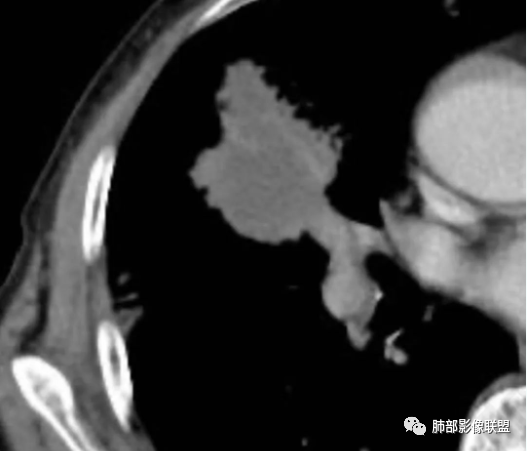

治疗前后对比CT:

放线菌病

八、影像特征:

1、慢性病程:慢性或亚急性化脓性肉芽肿性炎。

2、跨区域生长:放线菌不受解剖学屏障限制,可经胸膜进入胸腔或其他肺叶,可出现跨叶或累及胸膜、胸壁。

3、脓肿和坏死:局部扩散、多发脓肿、窦道形成,空气悬浮征。